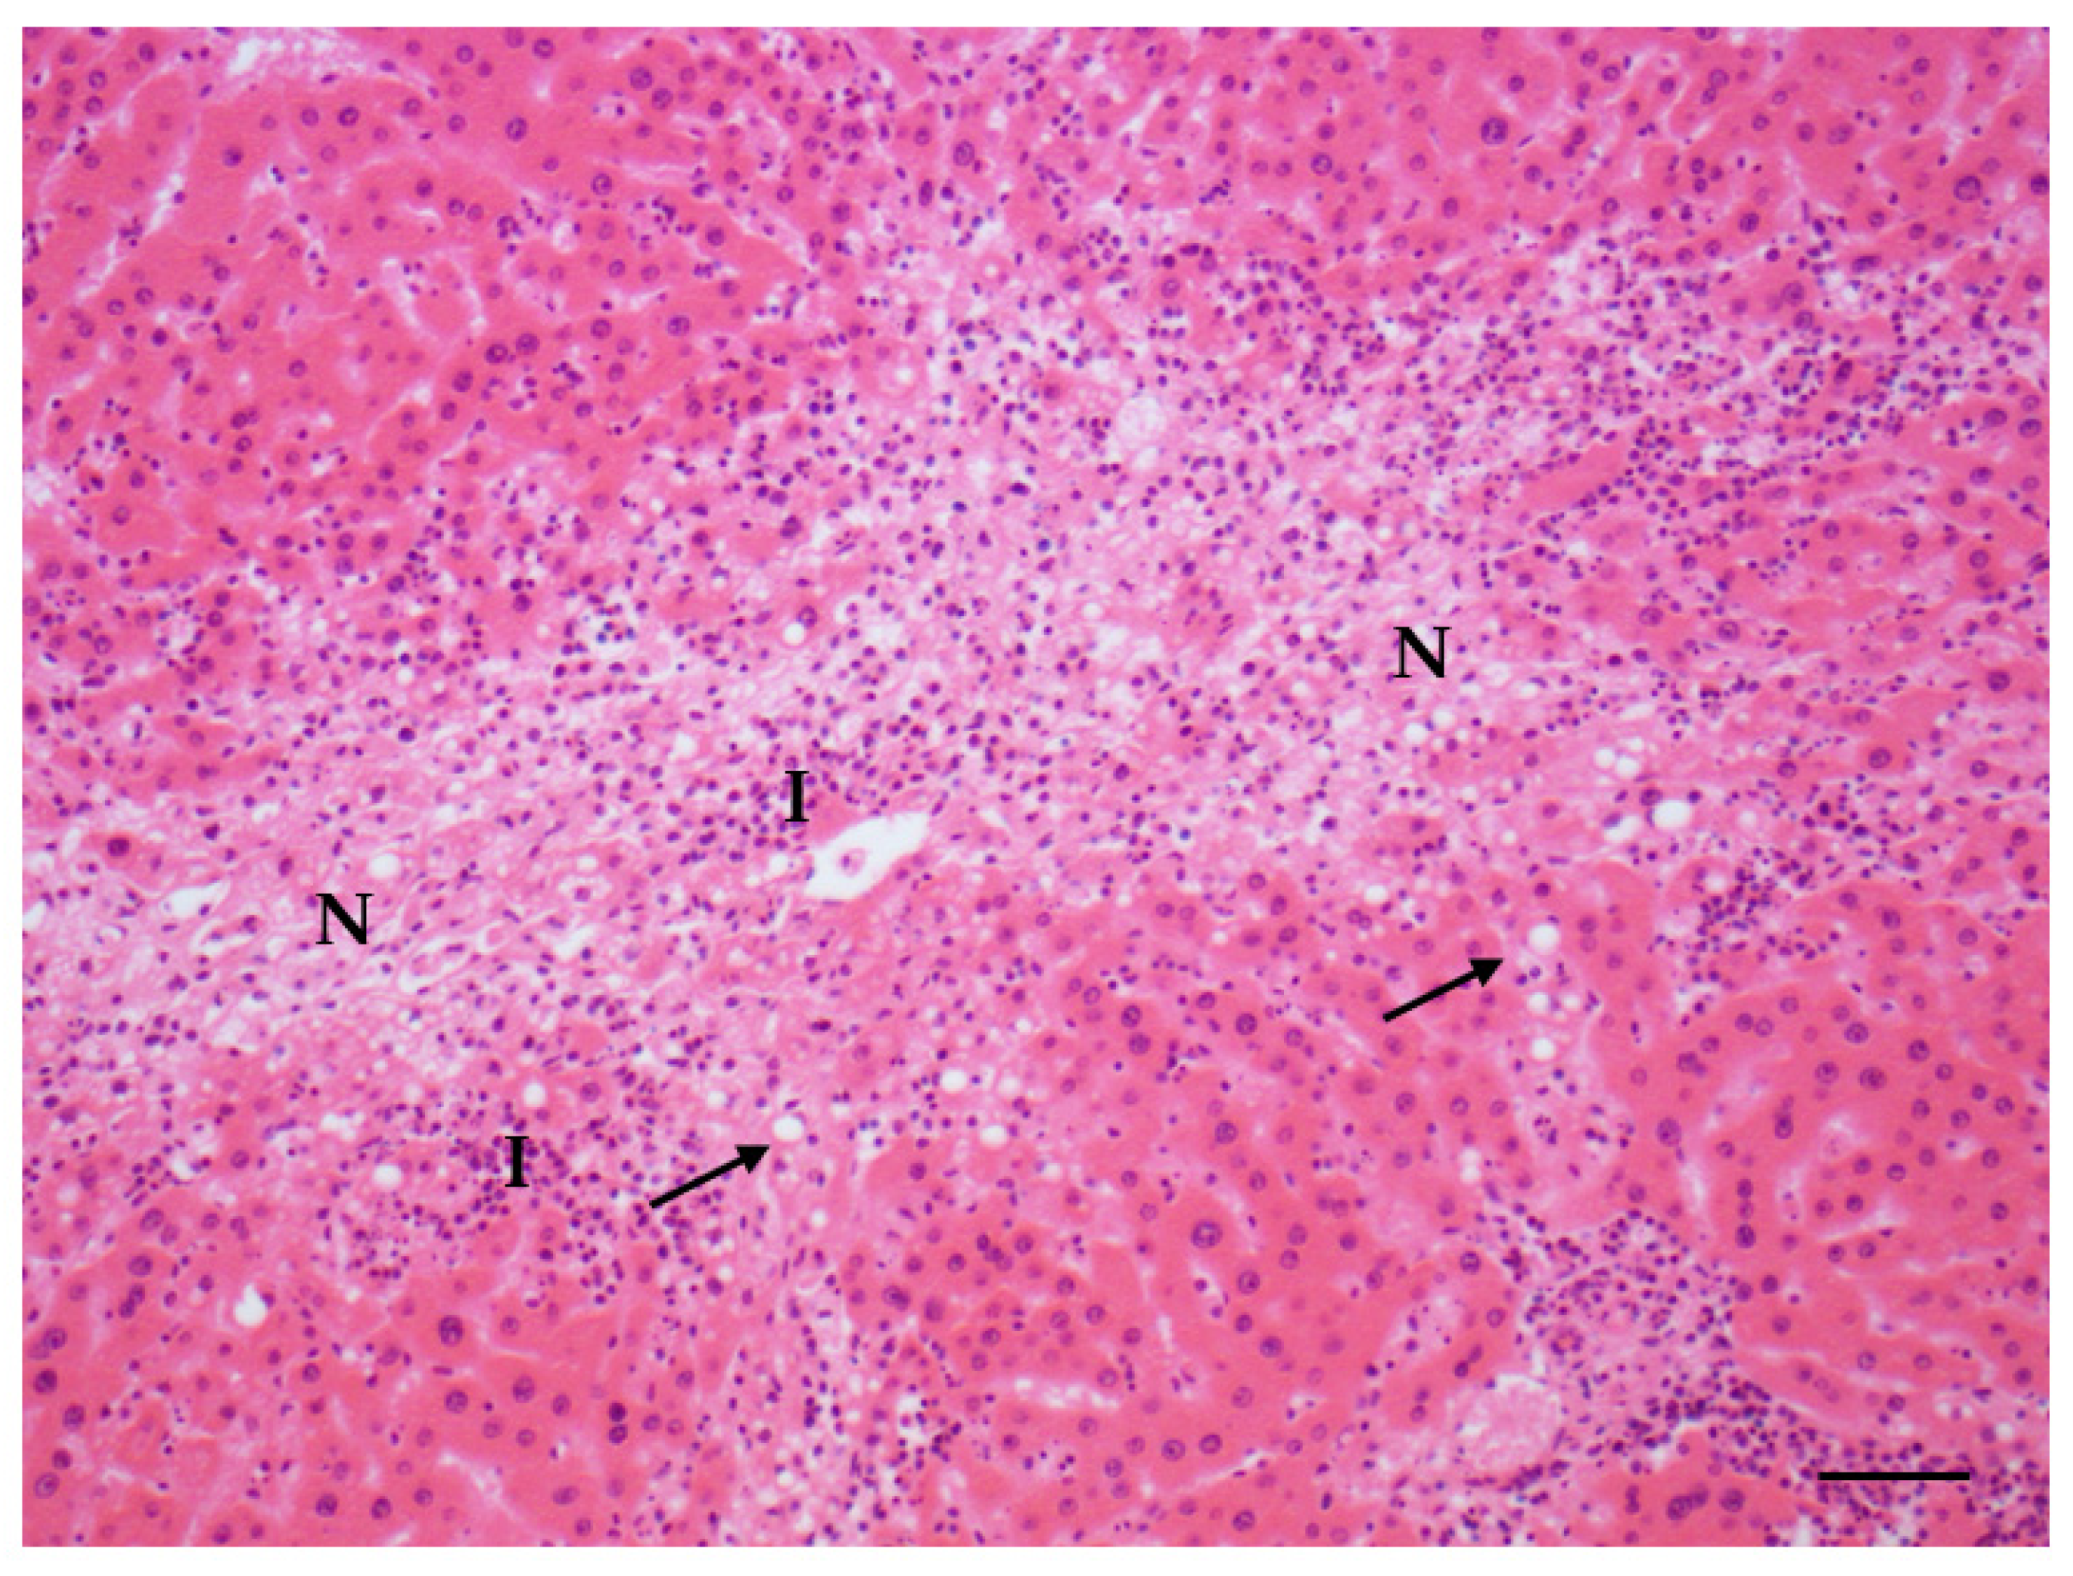

Figure 4.

Steatosis (arrows) associated with inflammation (I) and necrosis (N) in liver (AFB1 + ELFEMF treated female SD rat) (HE, 200×; scale bar 1 cm = 50 µm).